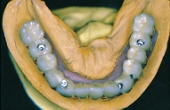

■CASE-4.(ボーンアンカーブリッジ)

Sinfonyは衝撃を吸収し破折しにくいので、骨組織へのダメージを軽減します。

[作成] [装着]